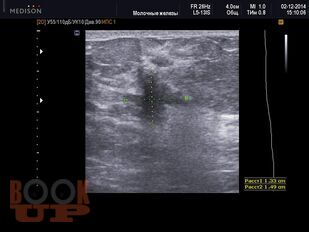

Методические аспекты ультразвукового исследования злокачественных образований молочной железы

В учебном пособии представлены методические подходы к ультразвуковому исследованию молочных желез, определены возможности ультразвукового метода исследования в выявлении и дифференциации вида злокачественных образований молочных желез, проведена оценка его роли и места в диагностическом алгоритме на основании изучения литературных данных и собственных наблюдений.